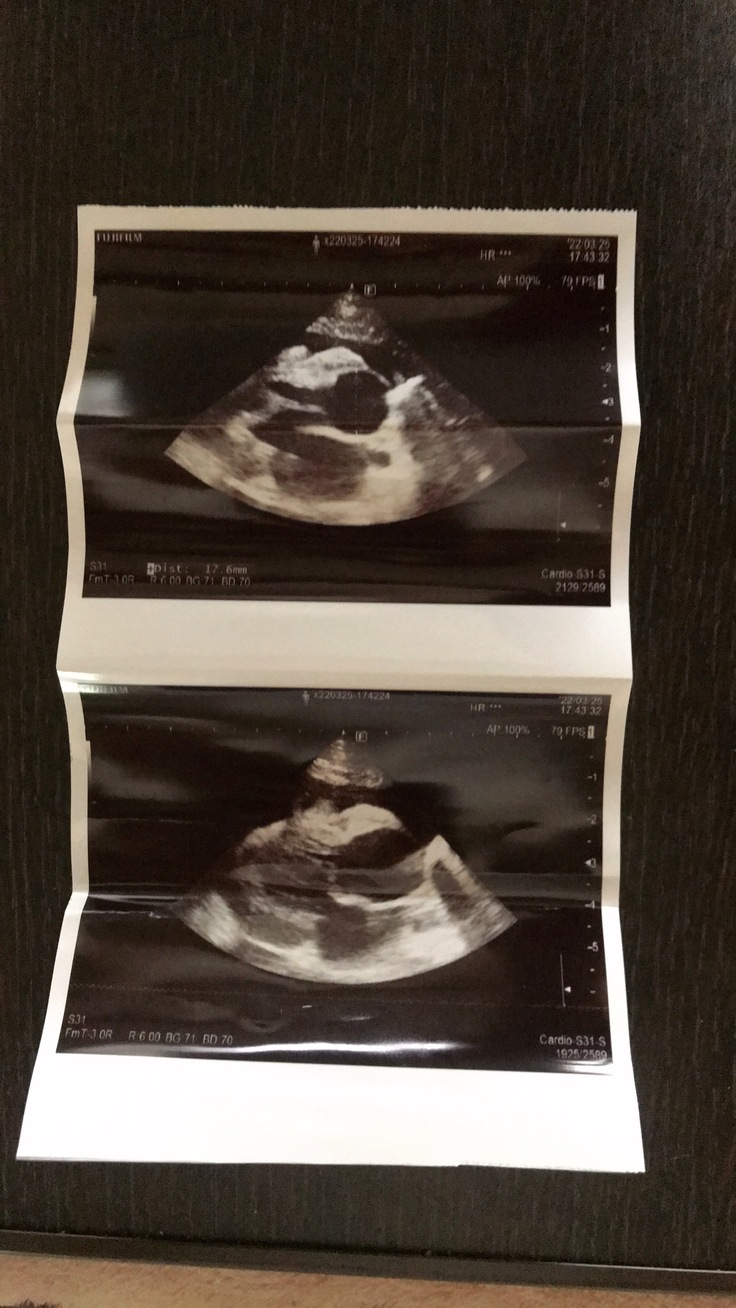

【エコー画像、胸水抜去量】

3月29日

外注検査結果の連絡があり

FIP混合タイプ陽性の診断を受けました。

※えんアニマルクリニックさんには

掲載許諾をいただいております。